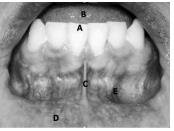

Considerando a fotografia intrabucal apresentada acima, julgue a pertinência da correlação da área indicada na figura com a respectiva descrição.

E: mucosa alveolar.